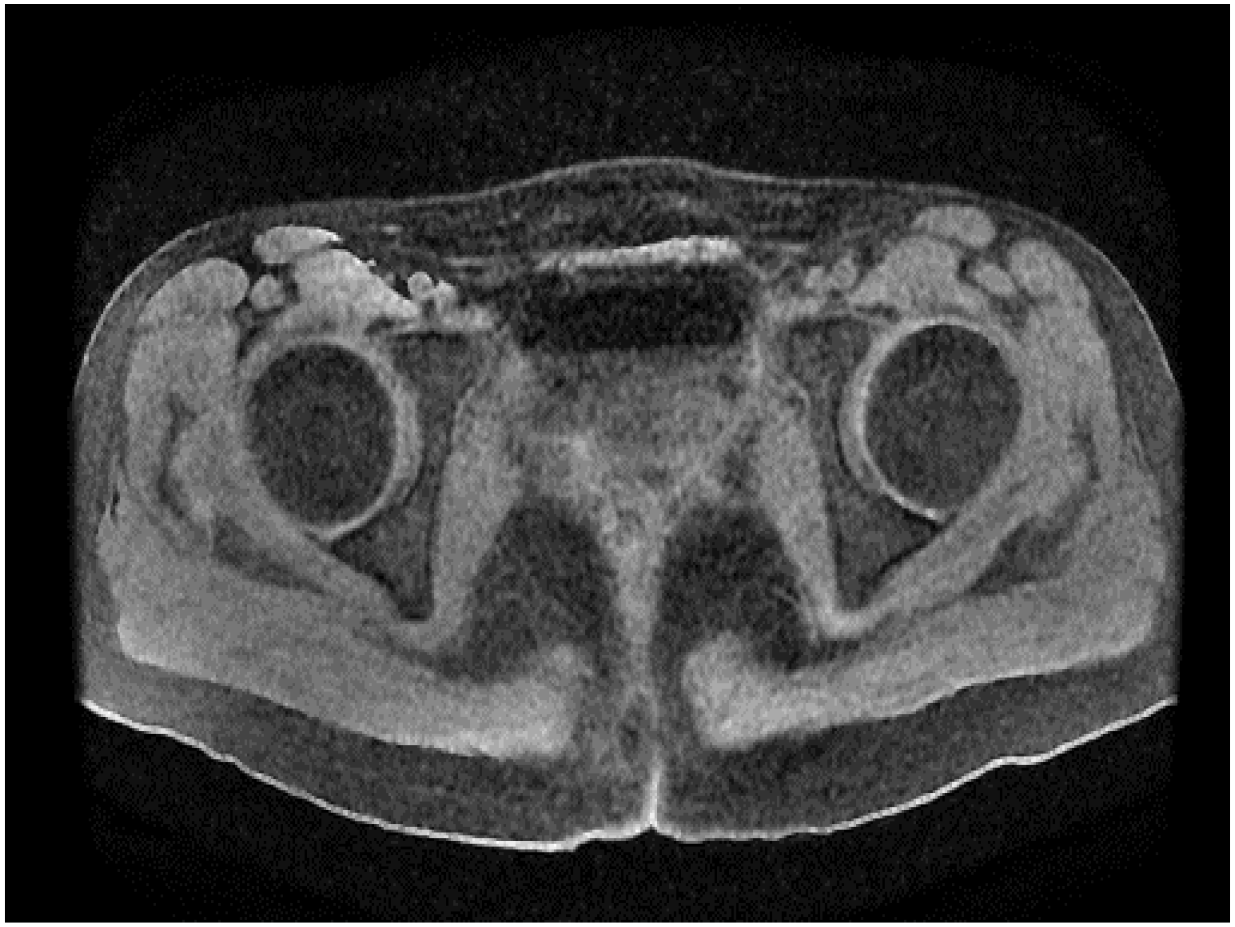

Following surgery, the patient received adjuvant combination chemotherapy with paclitaxel and carboplatin. After completing six cycles, magnetic resonance imaging (MRI), as illustrated in Figure 5, showed no evidence of tumour recurrence or metastatic lesions. The tumour marker CA125 decreased significantly from a preoperative level of 117.3 to 11.63 prior to chemotherapy and subsequently remained within the normal range. CA153 levels also demonstrated a declining trend and remained within the normal range in the most recent evaluation. However, although the CA199 level decreased by over half postoperatively, from 77.47 to 30.74, it consistently remained above the normal threshold of 30 during follow-up assessments. As a result, the patient has been placed under regular monitoring by her local oncologist.

Figure 5

Pelvic MRI findings following six cycles of adjuvant chemotherapy.

During the first postoperative year, follow-up assessments were undertaken at three-monthly intervals and comprised a general symptom inquiry, gynaecological examination, full blood count, pelvic ultrasonography, and contrast-enhanced computed tomography of the upper and lower abdomen and pelvis; a pelvic magnetic resonance imaging scan was additionally performed every six months. From the second year onward, the identical surveillance protocol has been maintained, albeit at six-monthly intervals. At each visit the patient reported no subjective discomfort, inspection of the vaginal vault revealed no palpable or visual evidence of residual or recurrent tumour, the full blood count remained unremarkable, and the serum tumour-marker panel stayed within reference limits. Serial pelvic ultrasound and magnetic resonance imaging demonstrated no structural abnormality, while the thoraco-abdominopelvic CT scans likewise showed no focal lesion or metastatic deposit.